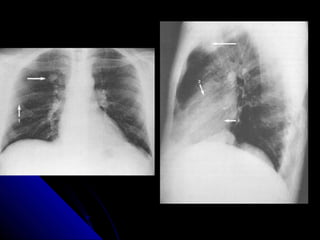

CCoollllaappssee

CCoommmmoonn ccaauussee ooff wwhhiittee lluunngg..

CCoollllaappssee lleeaaddss ttoo lloossss ooff vvoolluummee..

TThhee nnoorrmmaall llaannddmmaarrkkss aarree ddiissttoorrtteedd..

LLooookk aatt tthhee lluunngg ffiieellddss:: RR>>LL..

LLooookk aatt tthhee ddiiaapphhrraaggmm:: RR>>LL..

LLooookk ffoorr tthhee oobblliiqquuee ffiissssuurree..

TThhee hheeaarrtt aanndd tthhee ttrraacchheeaa..

TThhee bboorrddeerrss ooff tthhee hheeaarrtt..

30 CCoollllaappssee CCoommmmoonnccaauussee ooff wwhhiittee lluunngg.. CCoollllaappssee lleeaaddss ttoo lloossss ooff vvoolluummee.. TThhee nnoorrmmaall llaannddmmaarrkkss aarree ddiissttoorrtteedd.. LLooookk aatt tthhee lluunngg ffiieellddss:: RR>>LL.. LLooookk aatt tthhee ddiiaapphhrraaggmm:: RR>>LL.. LLooookk ffoorr tthhee oobblliiqquuee ffiissssuurree.. TThhee hheeaarrtt aanndd tthhee ttrraacchheeaa.. TThhee bboorrddeerrss ooff tthhee hheeaarrtt..